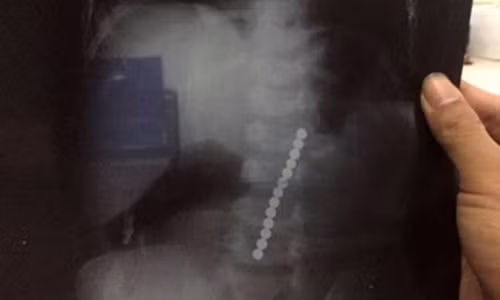

| Ảnh chụp X-quang viên bi cắm vào hộp sọ bé trai. Ảnh: BVCC |

Lúc phẫu thuật, bác sĩ phát hiện viên bi gần như xuyên hoàn toàn qua lớp xương sọ, làm vỡ mảnh xương sọ đâm vào nhu mô não, rách màng cứng, chảy dịch não tủy và dập nhu mô não trán. May mắn, viên bi kích thước to, lực súng bắn ra không cao nên viên bi không xuyên quá sâu vào bên trong nhu mô não.